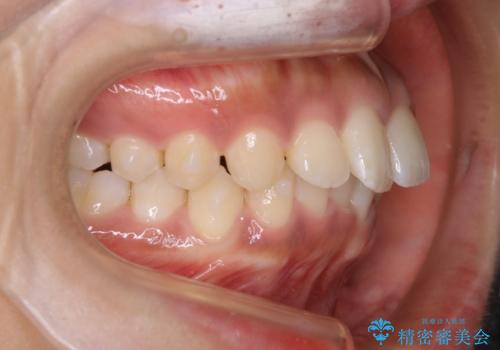

インビザライン矯正 歯を抜かずに出っ歯を改善!

- 出っ歯と前歯の隙間が空いていることを気にされて来院されました。

また、自然な感じで口元を下げていとのことでした。

奥歯のかみ合わせが問題なかったため、上顎の前歯の隙間を閉じるとともに、上顎の歯の側面を削ることをメインにして、出っ歯を改善する治療計画としました。

上顎の歯の傾きを変えるうえで、下顎の歯とのバランスのことも考え、下顎の歯の側面も削ることを加えています。

また、今回は口元を変えたい中に、劇的な変化は避けたいとのことだったので、抜歯をしない計画としています。

抜歯をしない場合、口元の変化は感じにくいですが、前歯の傾きが変わることで、口の閉じやすさは感じていただけたとのことです。

症例にもよりますが、本症例は奥歯のかみ合わせに問題がなかったので歯の側面を削ることメインに、前歯の傾きを改善することができました。

抜歯を行う場合や抜歯をしなくても奥歯の位置をずらす場合は、治療期間が長期化することが多いですが、今回は歯を削ることで改善できたため、短期間で治療を完了することができました。